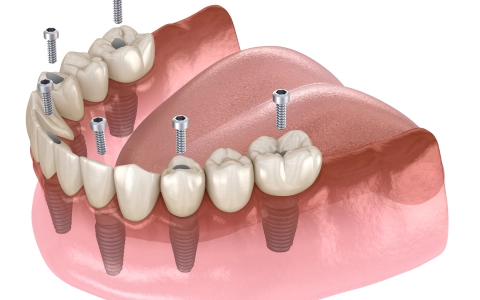

All On Six İmplant Tedavisi

All on Six, tam dişsiz çenede 6 implantla sabit, estetik ve güçlü protez sağlayan, hızlı iyileşen, uzun ömürlü modern bir implant tedavisidir rahat!